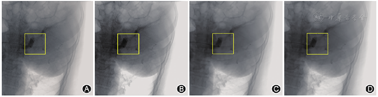

另外,该领域现有的方法大多只关注逐帧的二维图像去噪,在一定程度上丢失了图像序列的时间信息。为了同时处理血管造影成像中的时间与空间上的噪声,该系统提出一种新的三维/二维混合DnCNN方法。该模型以多帧为输入通道,综合各通道的信息得到最终结果。我们将该方法与一些业内最先进的算法进行比较,如在高斯分布噪声抑制方面取得良好效果的DnCNN算法[5,6],以及在传统透视中用于时域去噪的时间递归滤波器(temporal recursive filters,TRF)[7,8]。此外,我们实验中提出的网络和DnCNN使用的卷积层数目均为20层。与噪声图像相比,TRF的去噪效果有限。DnCNN和我们提出的方法可以有效地抑制背景噪声和椎体或血管图像中产生的噪声(图3, 图4)。

在降噪方面,DnCNN的降噪效果与我们提出的方法相当。但是在图4所示的感兴趣区域(region of interest,ROI)中,可以观察到DnCNN中的一些细节和边缘被过度平滑甚至出现模糊,从而导致细节信息的丢失,而我们提出的网络显示出可以更好地保留细节和精细结构的能力。

我们还评估了不同方法对低剂量血管造影图像的去噪效果(低剂量下曝光的剂量水平是正常剂量下的一半)。如图5和图6所示,我们还能够看到与正常剂量下的血管造影接近的图像效果。与TRF相比,DnCNN和我们提出的方法在噪声抑制方面显示出明显的优势。在TRF中,黄色矩形区域内的图像不易被识别。与DnCNN相比,我们提出的方法具有更好的细节保留和边缘锐化的能力(图6)。在低剂量血管造影中DnCNN还会出现过度平滑现象。另外,该患者AI优化前的普通参考剂量为0.25 mGy/s,优化后的辐射剂量为0.12 mGy/s,且经过本研究的AI优化后,图像质量不仅相比噪声图像得到显著改善,且与传统TRF相比,DnCNN去噪图像保留了更多的细节。TRF和DnCNN的去噪效果有限,我们提出的方法可以有效地抑制背景噪声,以及椎体或血管图像中产生的噪声[2,4]。